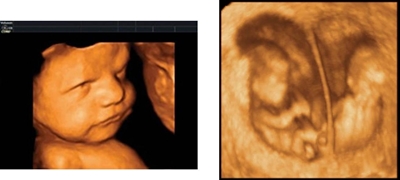

Ultrasonografia 3D

Método semelhante à ecografia, mas neste é possível ter uma visão a três dimensões do feto, percepcionando melhor o seu tamanho e também a percepção dos seus órgãos.

VANTAGENS

. Grande percepção do feto e dos seus órgãos;

. Detecção de anomalias na formação do feto e dos seus órgãos;

. Método não doloroso para a mãe para o feto;

. Resultados na hora.